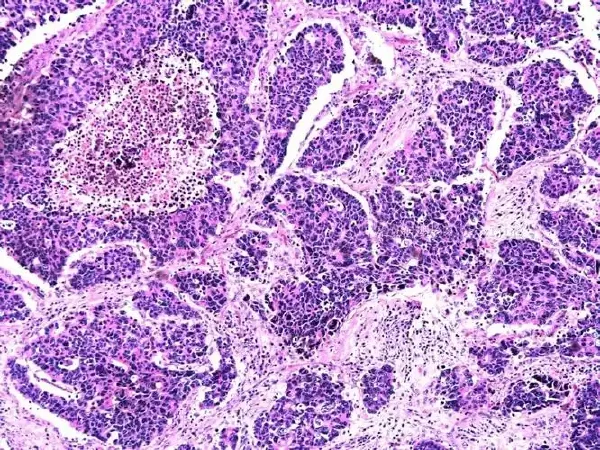

最具决定性的诊断方法是结肠镜检查,通过结肠镜可以直接观察结肠内的情况,并可在发现肿物的同时进行活检。活组织检查是确诊结肠肿物性质的金标准,通过显微镜下的病理学分析,可以确定肿物的良恶性及其具体类型,为治疗提供依据。